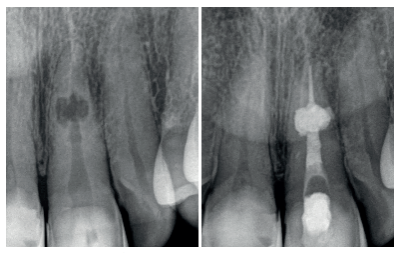

Para poder sellar de manera ortógrada se realizó una técnica híbrida descrita en la literatura12 , consistiendo en obturar la parte apical a la reabsorción con gutapercha, la zona de la reabsorción con un material biocerámico y el tercio coronal con gutapercha de nuevo. Se utilizó como cemento sellador AH Plus (Dentsply Maillefer, Ballaigues, Switzerland) con el cono maestro calibrado (25.06), realizando condensación vertical en el tercio apical, con la unidad alpha del sistema B&L (B&L Biotech, Fairfax, Estados Unidos). Obturados los últimos 4 mm, se procedió a adaptar el material biocerámico ProRoot MTA blanco (Dentsply Maillefer, Ballaigues, Switzerland) en la zona reabsortiva con la ayuda de diferentes pluggers manuales 35/70, 40/80, 50/100 (B&L Biotech, Fairfax, Estados Unidos) y vibración indirecta13, consiguiendo un mejor relleno de la cavidad reabsortiva. El tercio coronal a la reabsorción se obturó mediante la técnica de inyección con la pistola β de la marca B&L.

El sellado del límite amelocementario se realizó con un vidrio ionómero reforzado con resina (Ionoseal, Voco, Cuxhaven, Alemania), para evitar posibles riesgos de filtración coronaria, hasta que la paciente volviese con su referidor para la restauración definitiva (Figuras 5 y 6).

Se realizaron revisiones a los 6, 12, 18 y 26 meses, encontrándose la paciente totalmente asintomática, con signos de curación en los tejidos periapicales, observándose una regeneración ósea completa en la cortical vestibular (ausente en radiografia inicial). A los 26 meses se le dio el alta y se remitieron al referidor todas las pruebas diagnósticas y radiológicas (Figura 7).